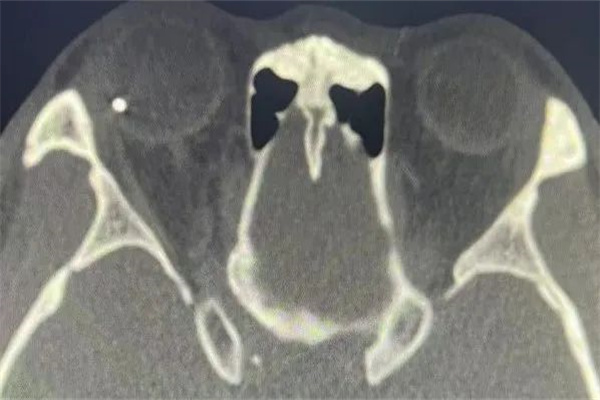

接診后,眼科楊清清主治醫(yī)師仔細對王申進行眼部檢查后發(fā)現(xiàn),他的右眼眼球破裂,球內(nèi)積血較多,懷疑眼球內(nèi)存留異物;而后,眼眶CT及歐堡掃描激光眼底照相結果顯示,一個直徑約4mm的金屬異物擊穿角膜、前房、虹膜、晶狀體、玻璃體并嵌頓于顳側(cè)視網(wǎng)膜上,也就是說,異物直接把眼球中所有的重要組織全部貫通。最重要的是人體中含水量最高的器官則是眼球,眼球內(nèi)組織絕大部分都是由水分構成,異物在眼內(nèi)很快便會生銹、粘連、牽拉,若不及時取出異物手術治療,可能導致眼內(nèi)感染、眼球萎縮,最終失去光明,且另一只健眼還有發(fā)生交感性眼炎的可能性。